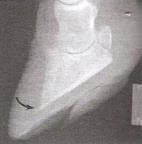

Lateral Görünüm

Dorso/plantar Görünüm